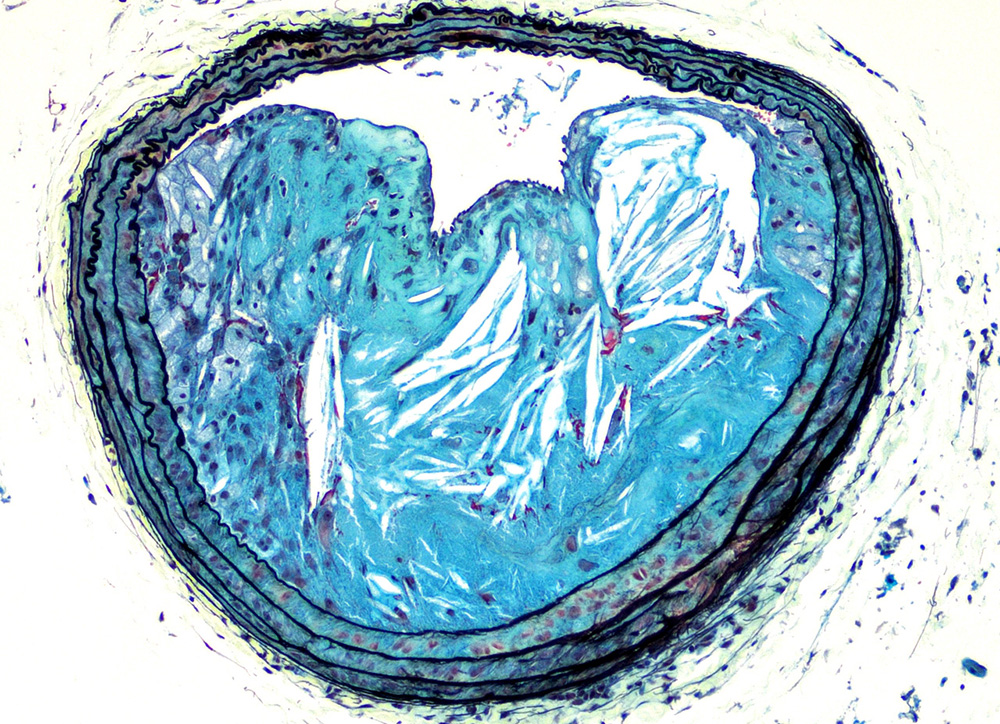

Atherosclerosis starts with fatty streaks appearing in blood vessel walls. As the atherosclerotic lesion grows, inflammation provoked by obesity and recruitment of immune cells can speed the growth of the plaque.

Certain white blood cells, particularly monocytes that participate in inflammation, and macrophages, or "big eaters" that are supposedly the bloodstream's cleanup crew, are among the culprits. They can become overladen by engulfing lipids, and can turn into foam cells. These cells gather, and then perish. The core of the lesion fills with dead cells and other debris. If it ruptures, a clot can rapidly form in the vessels of the heart or brain.

Probably because of all this influence on white cells, the lesions did not grow with the rapidity expected in diabetes and metabolic syndrome. The researchers also saw that lesions with debris-filled cores were less common in these mice.